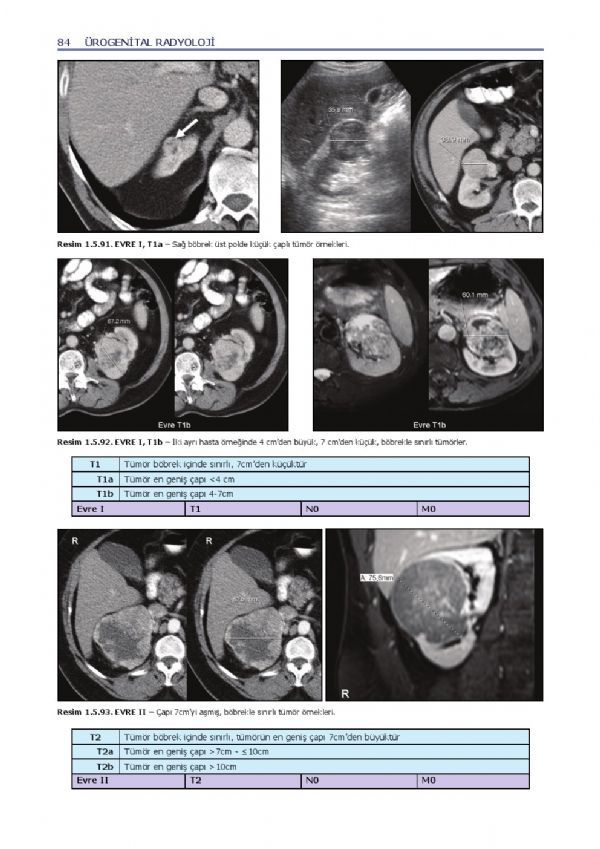

Ürogenital Radyoloji